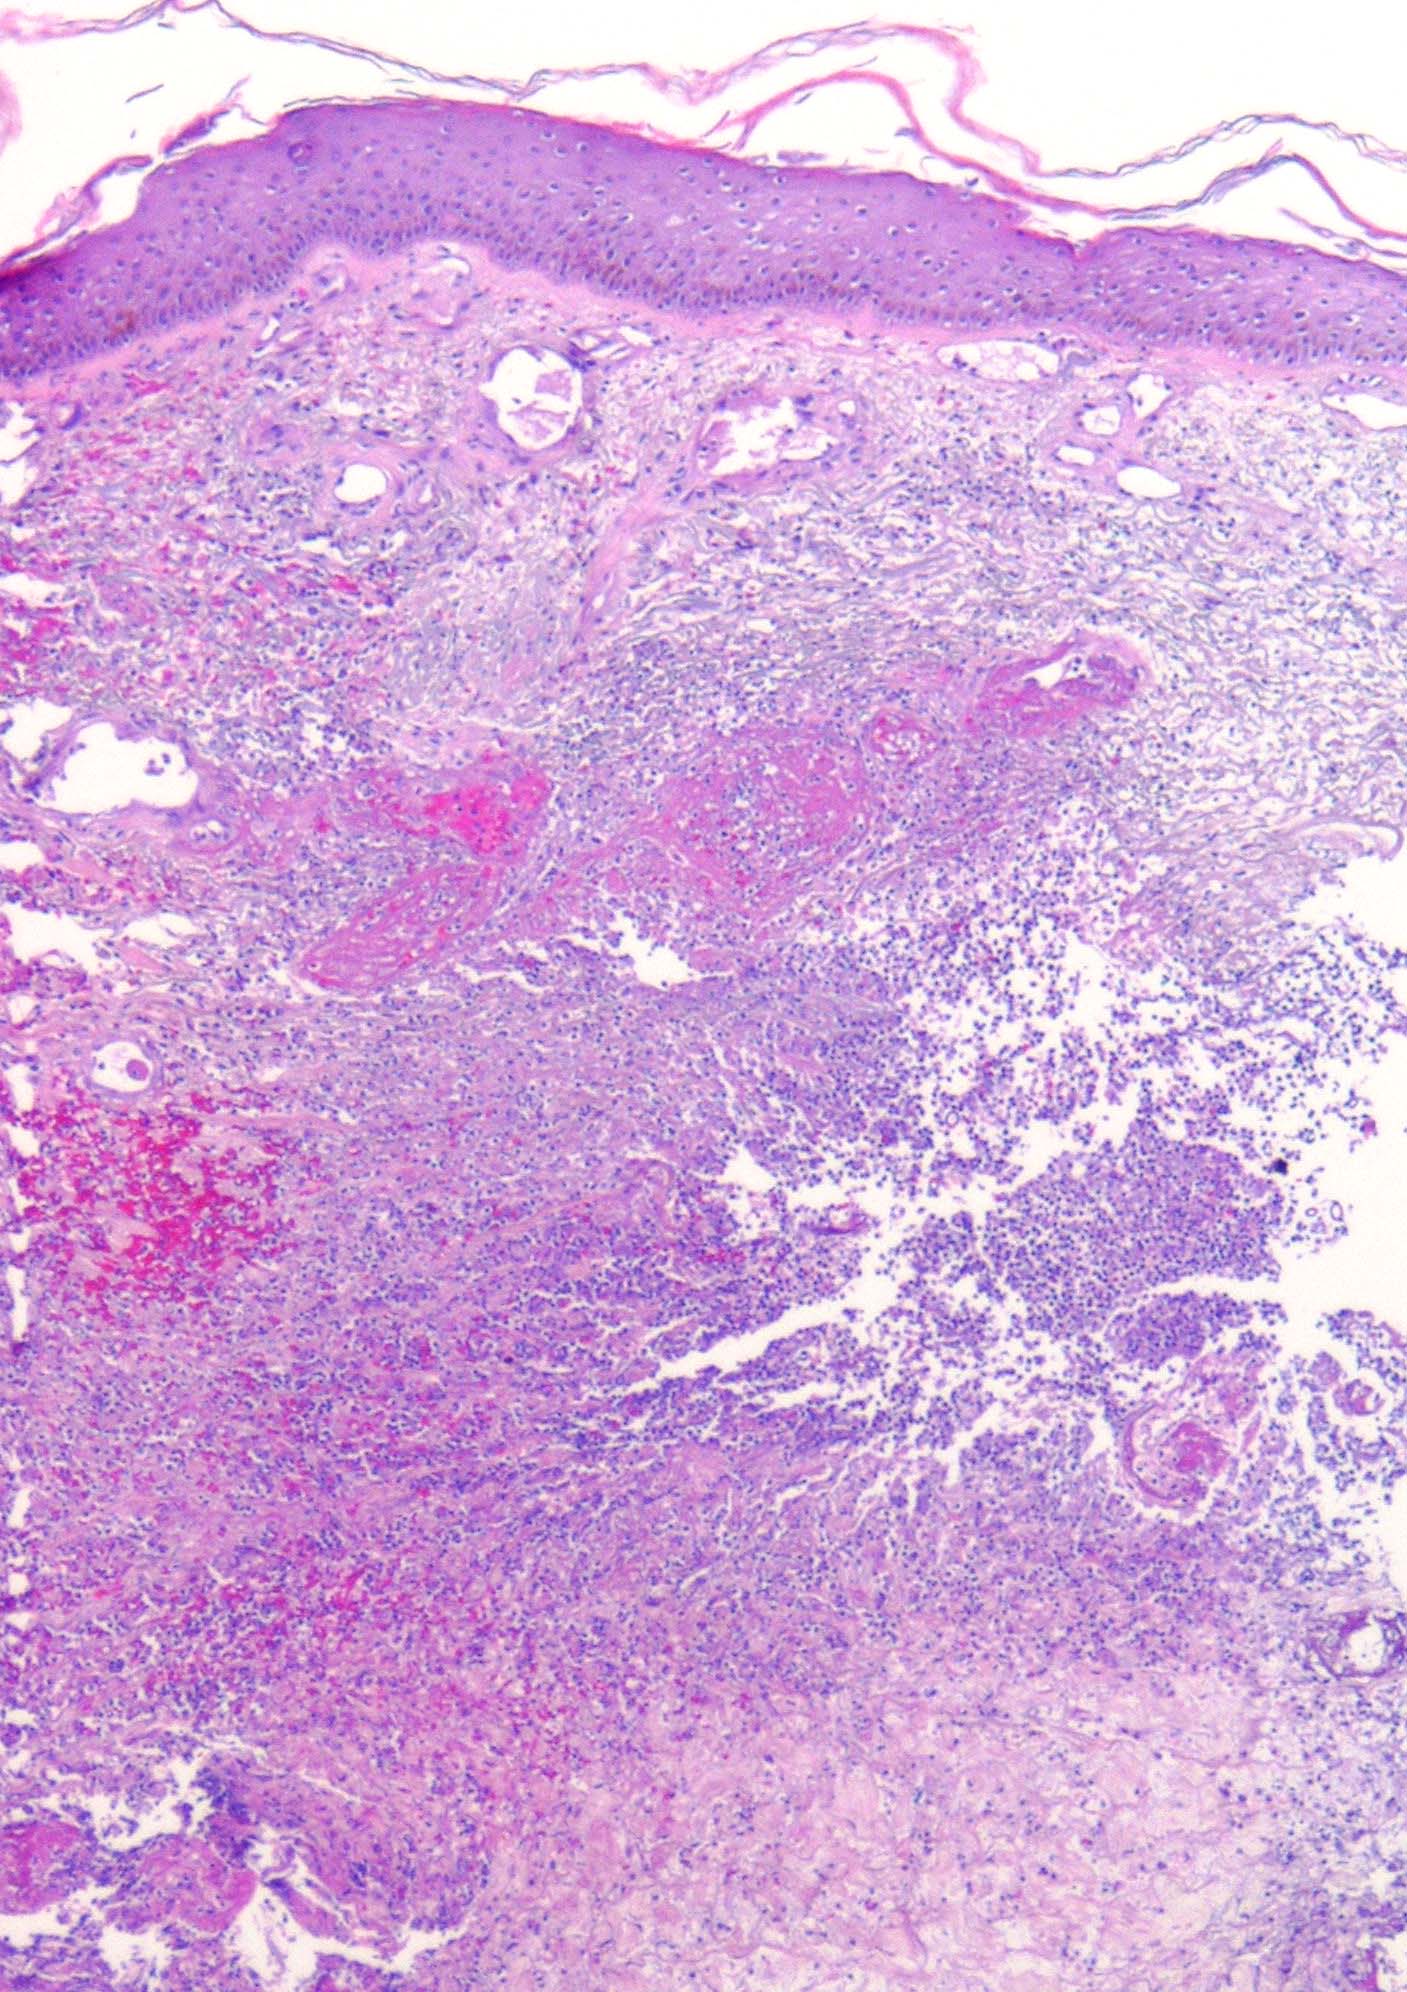

Zygomycosis =فطار عفني